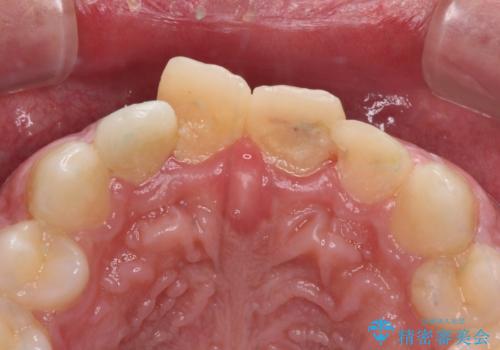

損傷がひどく、前歯4本と広範囲であったため、症状やレントゲン写真、検査結果が一致せず、定期的に経過を見ながら診断していくこととしました。

右側前歯は歯根が短くなり、パンチング状に歯根に透過像が認められたため、予後不良と判断し抜歯することとしました。

当初のレントゲン写真では根尖部に骨透過像が認められた両サイドの2歯は、歯髄の正常な反応が認められたためそのまま保存し、左側前歯は歯髄が失活していたため根管治療を行うこととしました。

抜歯後の欠損部はブリッジにて補綴治療を行うこととしました。

事故直後のレントゲン写真では全ての歯の根尖部に骨透過像が認められましたが、治療後には全ての透過像がなくなっていました。